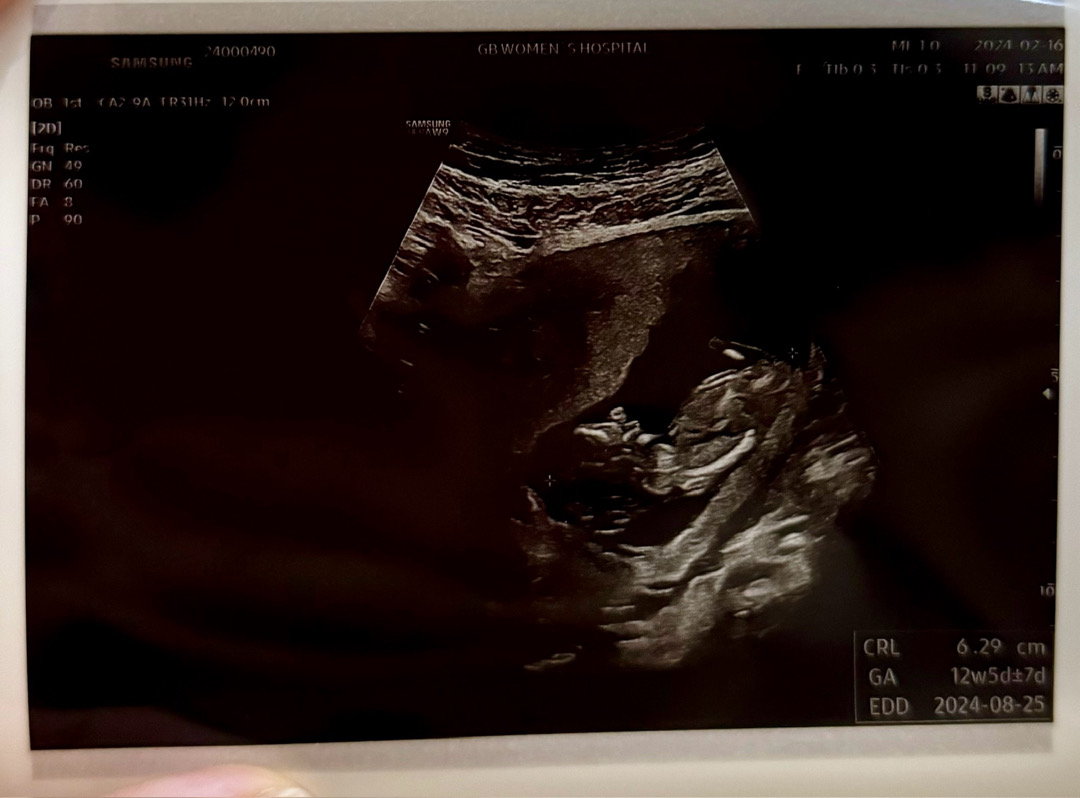

12주 1일차 각도법 문의합니당😍

입체초음파만 계속 쳐다보다가 아!싶어서 혹시!하는 맘에 올려봅니당ㅋㅋㅋ 각도법 알아보는 분들 댓글 살포시 남겨주실 수 있으실까요? >_<*

딸 가능성이 조금 더 있어보여요